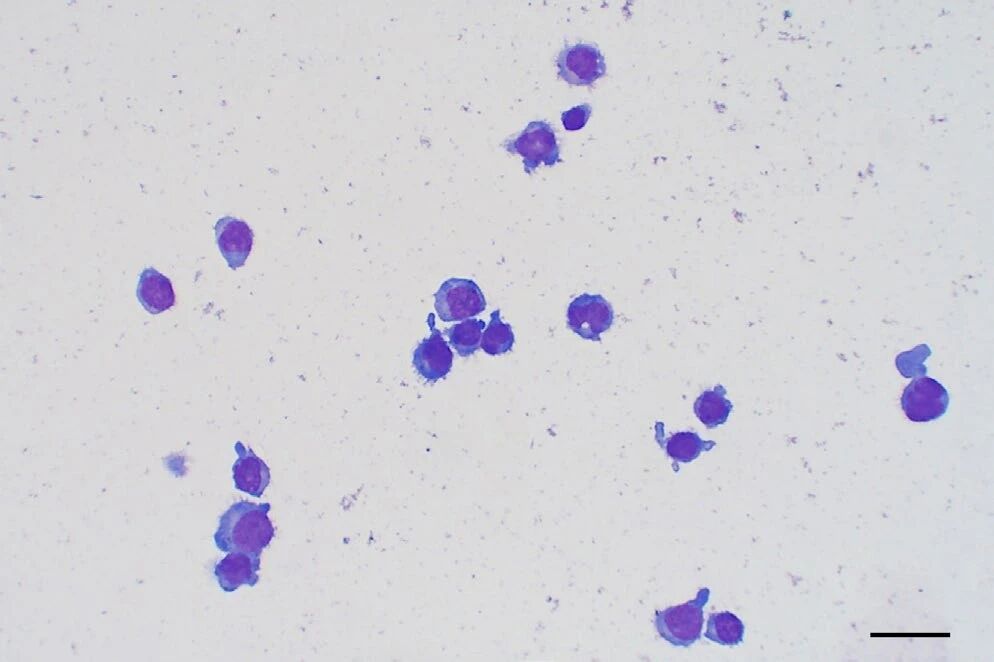

通过腰穿获得的脑脊液分析显示,淋巴细胞明显增多(837个/μL,蛋白14843.8mg/L),以中等和大型淋巴细胞为主,小型成熟淋巴细胞数量少(<20%),有罕见的有丝分裂象(下图)。这些发现提示为中等到大细胞淋巴瘤。

↑ 脑脊液的细胞学分析显示高度细胞增生,以中型和大型淋巴细胞为主,且小型成熟淋巴细胞数量较少。

↑ 脑脊液显示出大圆细胞(星号),伴有少量中等嗜碱性、部分空泡化的细胞质。也可以看到有丝分裂像(箭头),以及小淋巴细胞(三角)。

脑脊液细胞学检查显示轻度淋巴细胞性细胞增多(22×10³/μL,蛋白质1840.3 mg/L),以大型圆形细胞为主,胞浆呈中等蓝色,核呈中至大型椭圆形,染色质呈颗粒状(下图)。

↑ 脑脊液显示低至中等的细胞增多,主要为大而圆的细胞,具有适量的蓝色细胞质和中等至大型、不规则的圆形细胞核,核内有细颗粒的染色质。